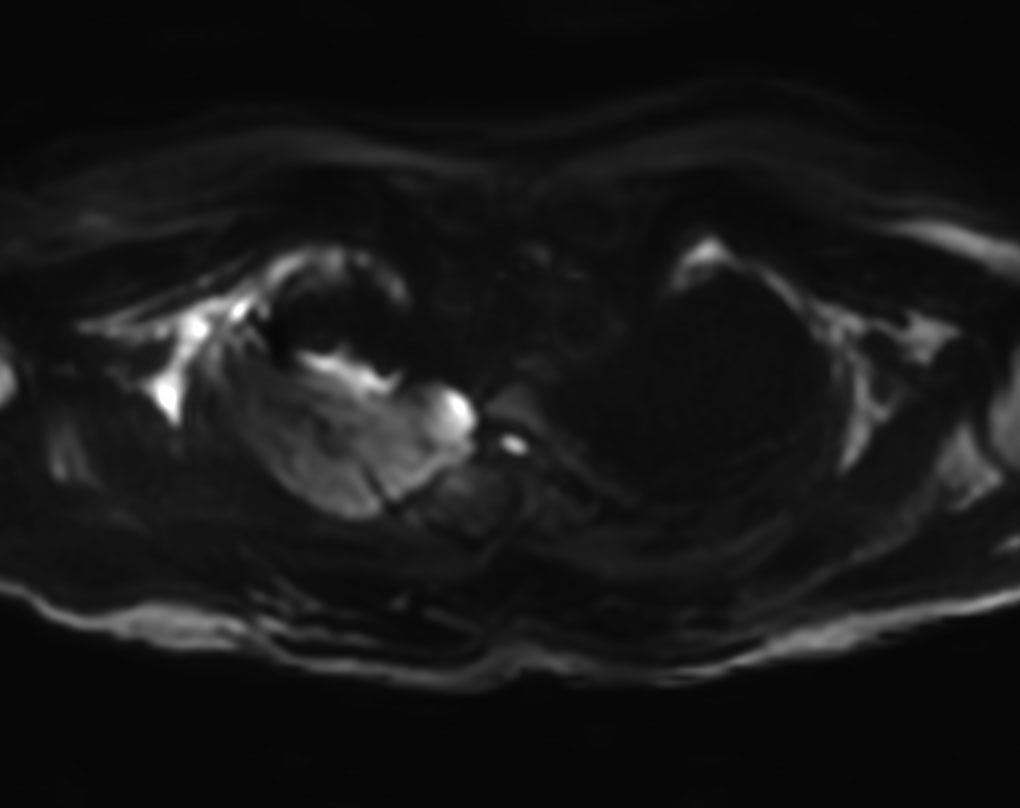

Axial DWI (b800)

Axial DWI (ADC)